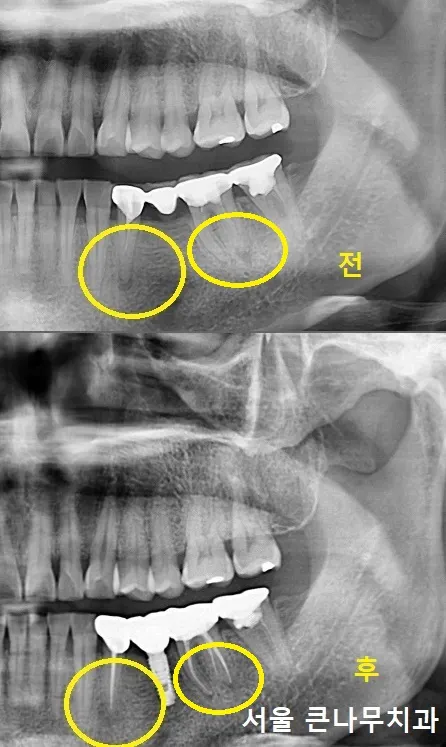

반대쪽인 오른쪽도 비슷한 상황이라서 몇달 후에 다시 내원하셨습니다.

오른쪽 큰 어금니는 뿌리가 파절되어 있어 발치를 진행하게 되었습니다.

3개로 연결되어 있던 브릿지 보철 제거가 이루어졌고, 이와 함께 발치 후 당일 즉시식립으로 임플란트를 바로 심어주었고 뼈이식도 함께 해주었습니다. 작은 어금니는 지르코니아 크라운으로 다시 수복해주었습니다.